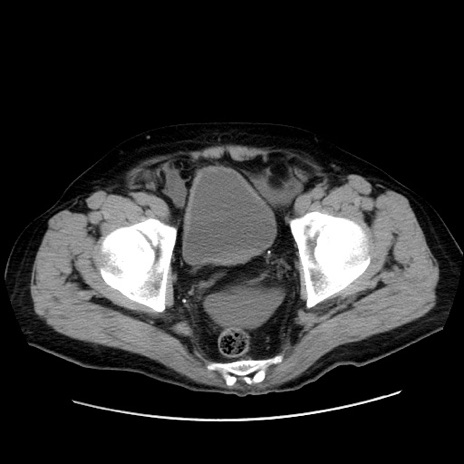

症例30(横断像)

【症例】80歳代男性

【主訴】臍周囲痛

【現病歴】約6時間前から臍下部痛が出現。次第に腹部膨隆・背部痛も生じてきたため来院。背部痛の場所は変化しない。

【既往歴】腎盂腎炎

【身体所見】意識清明、BT 36.3℃、BP  131/87mmHg、P 87bpm、SpO2 100%(RA)、臍周囲自発痛・圧痛あり、反跳痛なし、自発痛部位に一致して板状硬あり、腹部膨隆、腸雑音減弱、CVA tenderness両側陰性。

【データ】WBC 19600、CRP 0.33